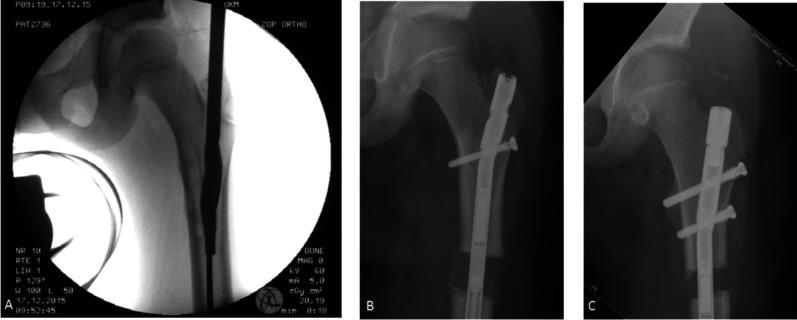

QUESTIONS/PURPOSES: (1) Is femoral lengthening with magnetically driven antegrade intramedullary lengthening nails accurate and precise? (2) What are the most common complications of treatment? (3) What factors are associated with unplanned additional surgery?

We retrospectively analyzed the longitudinally maintained database of our orthopaedic teaching hospital to identify all patients who underwent surgery for leg length discrepancy (LLD) between October 2014 and April 2019. In total, we surgically treated 323 patients for LLD of 2 cm or more. Of those 55% (177 of 323) were treated with distraction osteogenesis with magnetically driven intramedullary lengthening nails, 18% (59 of 323) with external fixation, and 27% (87 of 323) with epiphysiodesis around the knee. Based on that, 29% (93 of 323) of patients underwent unilateral femoral distraction osteogenesis with magnetically driven antegrade femoral lengthening nails and were eligible for analysis. No patient was excluded, and 3% (3 of 93) were lost before the minimum study follow-up of 2 years, leaving 97% (90 of 93) for analysis. Patients with a distal femoral deformity were treated via a retrograde femoral approach (10% [33 of 323]) or with external fixators (3% [10 of 323]) and were not included in this study. Distraction osteogenesis with magnetically driven intramedullary lengthening nails was not considered for patients with deep tissue infection, those with bone dimensions considered to be too small in relation to the available implants, and for patients younger than 8 years. This study included 90 patients (44 females, 43 left femora) treated for a median (interquartile range) preoperative LLD of 39 mm (32 to 52) at a median age of 15 years (14 to 17). The same limb lengthening system was applied in all patients. The median (IQR) follow-up was 35 months (24 to 78). Data were acquired through a chart review performed by someone not involved in the surgical care of the included patients. Data acquisition was supervised and curated by two of the involved surgeons. Accuracy was calculated as 100 - [(achieved distraction in mm - planned distraction in mm) / (planned distraction in mm) x 100] and precision as 100 - (relative standard deviation of accuracy). Treatment-associated complications were summarized descriptively and characterized as complications resulting in unplanned additional surgery or those not resulting in unplanned surgery. To analyze the risk of unplanned additional surgery by entity, we calculated odds ratios (ORs) comparing the incidence of unplanned additional surgery in the different entity cohorts with the idiopathic LLD cohort as a reference. By calculating ORs, we analyzed the risk for unplanned additional surgery depending on sex, age, surgery time, and previous lengthening. Due to the lack of long-term evidence about motorized lengthening nails remaining in situ and concerns about potential implant-related adverse effects, removal was routinely scheduled 1 year after consolidation. For implant removal, 92% (83 of 90) of patients underwent planned additional surgery, which was not recorded as an adverse event of the treatment. Ninety-seven percent (87 of 90) of patients completed lengthening with the implant remaining in situ until the end of distraction. The median (IQR) distraction length was 37 mm (30 to 45) with a median distraction index of 0.9 mm/day (0.7 to 1.0) and median consolidation index of 31 days/cm (25 to 42).

RESULTS

The calculated accuracy and precision were 94% and 90%, respectively. In total, 76% (68 of 90) of our patients experienced complications, which resulted in 20% (18 of 90) of patients undergoing unplanned additional surgery. The most common complication overall was adjustment of the distraction rate in 27% (24 of 90) of patients (faster: 16% [14 of 90]; slower: 11% [10 of 90]) and temporary restriction of knee motion, which occurred in 20% (18 of 90) of our patients and resolved in all patients who experienced it. The most serious complications were bacterial osteomyelitis and knee subluxation, which occurred in 3% (3 of 90) and 1% (1 of 90) of our patients, respectively. With the numbers available, we found only one factor associated with an increased likelihood of unplanned additional surgery: Patients with postinfectious LLD had higher odds of unplanned additional surgery than patients with idiopathic LLD (7% [1 of 15] versus 50% [3 of 6], OR 14.0 [95% CI 1.06 to 185.49]; p = 0.02). However, we caution readers this finding is fragile, and the confidence interval suggests that the effect size estimate is likely to be imprecise.

CONCLUSION

Femoral distraction osteogenesis with magnetically driven antegrade intramedullary lengthening nails appears to be an accurate and reliable treatment for femoral lengthening. However, depending on the etiology, a high risk of unplanned additional surgery should be anticipated, and a high proportion of patients will experience temporary joint stiffness. We recommend close orthopaedic follow-up and physiotherapy during treatment. This treatment of LLD can be considered alongside other nails, external fixators, and epiphysiodesis. Multicenter studies comparing this with other approaches are needed.